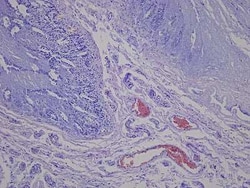

Novus Biologicals™ Small Intestine Jejunum Tissue Slides (Diabetes)- Paraffin

| För användning med (applikation) | Immunohistochemistry (IHC), Immunohistochemistry (Paraffin), ISH, Dual RNAScope ISH-IHC |

| Målspecificitet | Small Intestine Jejunum |